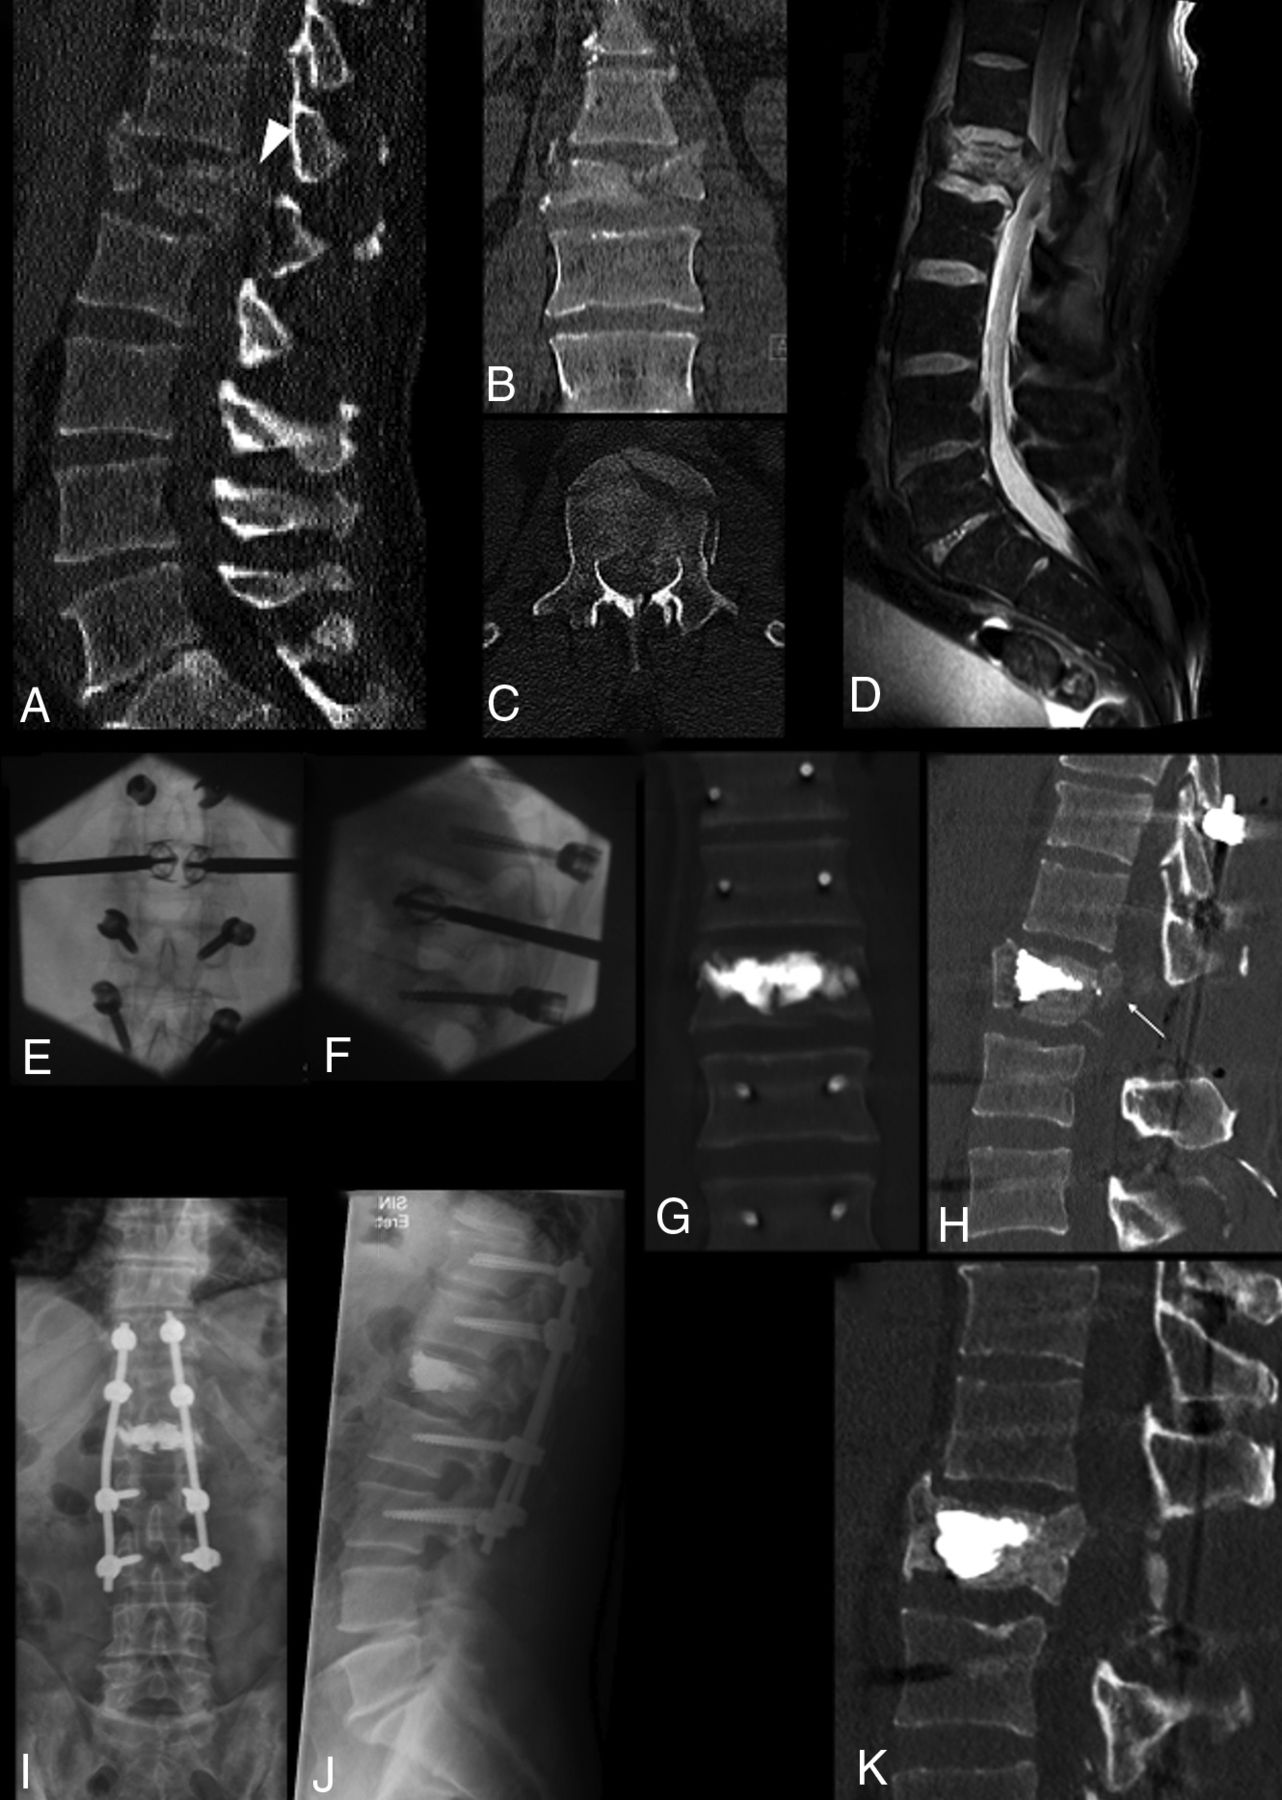

Three different cases (A–C), (D–G), and (H–J). A–C, Treatment with the SpineJack of a traumatic incomplete burst fracture of T12 in a 55-year-old man with posterior wall retropulsion (arrow, A) and junctional kyphosis. Postoperative CT shows vertebral height restoration, central canal clearance through retropulsed fragment correction (arrowhead, C), and kyphosis correction. D–G, Treatment with the SAIF technique of a traumatic T10 fracture in a 78-year-old man with osteoporosis with >50% height loss and posterior wall retropulsion (arrow, D), with effective height restoration and posterior wall reposition (arrowhead, G). H–J, Treatment of an L1 osteoporotic fracture with bone subsidence (arrows, J) around the cement cast at 1-month follow-up, not compromising alignment and curvature. The patient was asymptomatic.

Follow-Up

Beyond the postprocedure clinical assessment, spine plain films, and CT within 10 days, 39/51 patients (41/53 levels) had an extended clinical and imaging follow-up, at least with standing spine plain films, at multiple and variable time points, ranging from 1 to 36 months postprocedure (mean, 8 months). In 19/41(46%) levels, the postprocedure VBH was fully maintained; in 19/41 (46%), mild subsidence of the superior or inferior endplates was noted (Fig 3) with no convincing impact on alignment and kyphosis, while in 3/41 (8%), a recurrent VBH collapse of the target level was noted. In the follow-up group, 22/41 levels were studied with a cross-sectional imaging technique (8 with MR imaging and CT, 11 with CT, and 3 with MR imaging), and PWR could be assessed. Fourteen of 22 showed stability of the PWR correction compared with the postoperative CT, while 8/22 showed a recurrence in PWR. Of these 8 cases, 2 were associated with refracture of the target level, while 6 were associated with subsidence of the treated vertebra at follow-up. No retreatment was necessary at AKP-treated target levels. Clinical follow-up showed no neurologic deterioration.